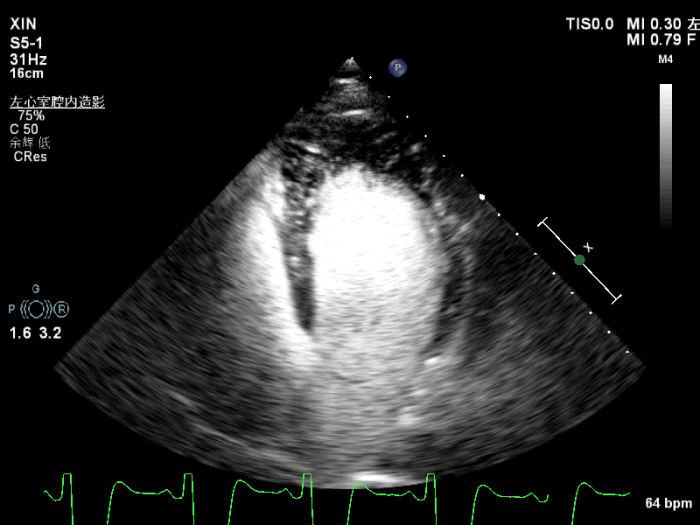

经胸超声心动图提示,心尖四腔心:心尖部心肌及心内膜显示模糊不清。